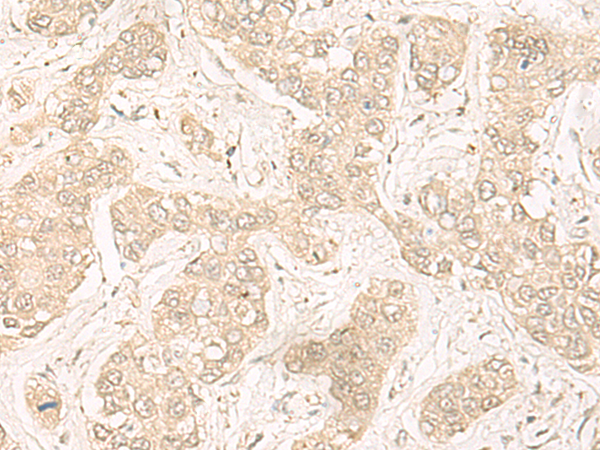

IHC positive control:

Human liver cancer

IHC Recommend dilution:

30-150